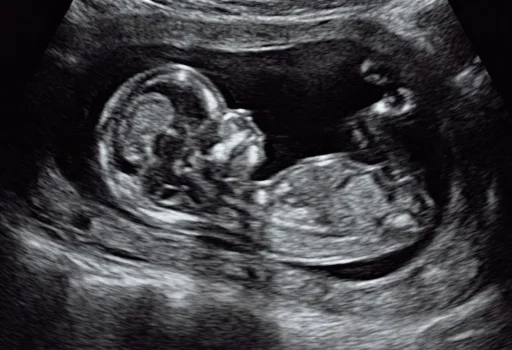

Anomaly scan / TIFFA scans (18-22 weeks pregnancy)

This is done between 18-22 weeks pregnancy . This is the most important and most detailed scan. The scan is mainly focused on examining the development of the baby completely from head to toe and make sure there is no abnormality in the structures. If it is done too early few structures may not be developed and if done too late even if there are abnormalities we may not be able to do anything about it. This is a very specialised scan like the NT scan and needs expertise , good machine and detailed examination to make sure everything is normal. If any abnormality is found, the abnormality , why it occurs, risk of genetic problems, further tests to be done, outcomes for the fetus , what treatment can be done and risks will be explained to the parents in detail. They will be given all options and help to manage the pregnancy along with a discussion with their referring doctor. In addition to checking for structural abnormalities , risk of growth problems, genetic abnormalities , pre term delivery and issues of inadequate growth will also be checked for .